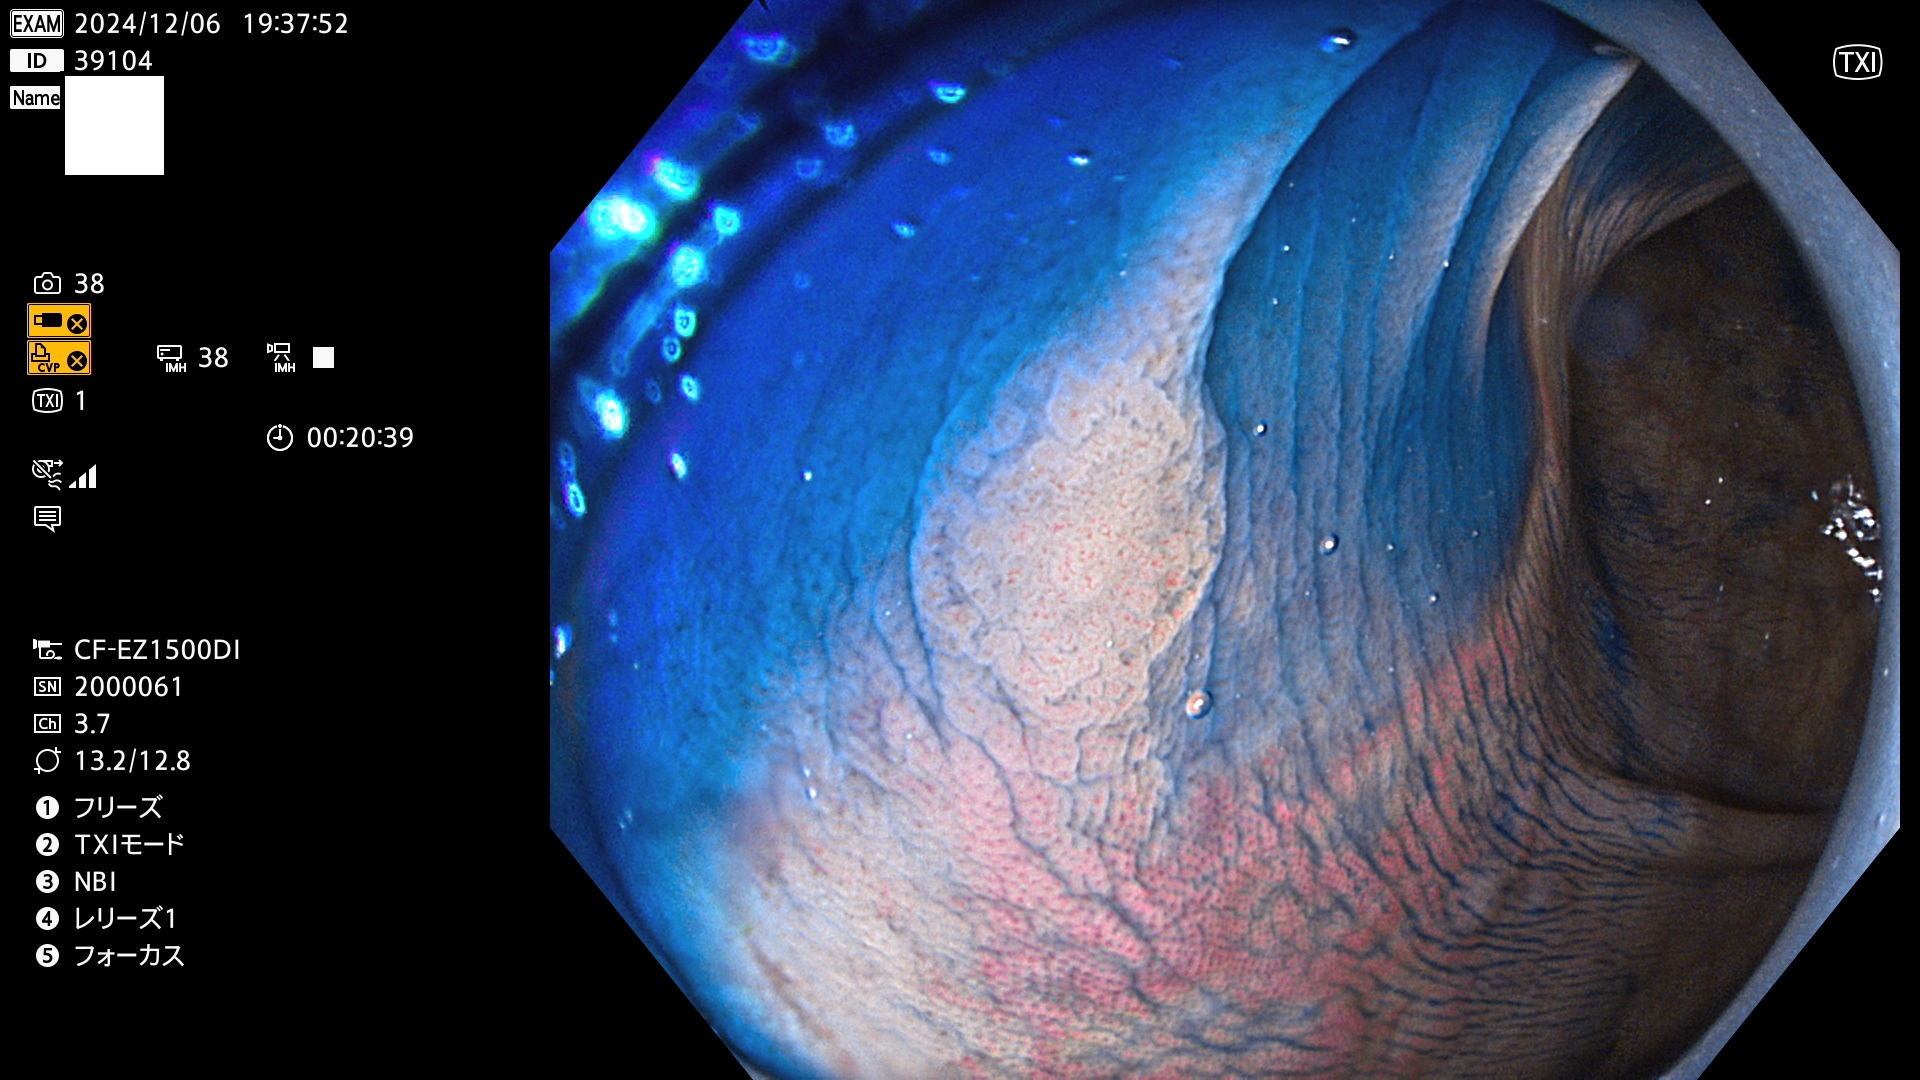

今週のUb、Uc型腺腫

完全に平坦な物をUb、陥凹している物をUcと呼びます。最も発見が難しく危険な病変です。

専門的)何故、陥凹していると危険? 癌遺伝子の変異が蓄積すると細胞分裂が盛んになり隆起するのでは?と通常は思われるでしょう。しかし実際は逆です。これは2022年の記事にある「細胞はストレスに直面したら細胞分裂を止める(細胞老化に入り休眠する)という生命の基本的現象」によるものです(Oncogene Stress)。細胞老化を起こすのが癌抑制遺伝子で、この安全装置(ブレーキ)が壊れると癌になります(休眠からの覚醒)。ですから陥凹は「まだ癌では無いが癌化の直前」を意味します。特に「小サイズなのに陥凹している」病変は短期間に腫瘍進化(IntraTumor Heterogenity⇒2021年記事)が起きたことを意味します(=ゲノム不安定性

毎週の検査(木・金・土・日)に発見されたUb、Uc型・腺腫を、その週の日曜の夜にUPし1週間、提示します。

抽出の対象期間 2024年12月5日〜12月8日の4日間(48件の検査)4件 (4/48=8%)